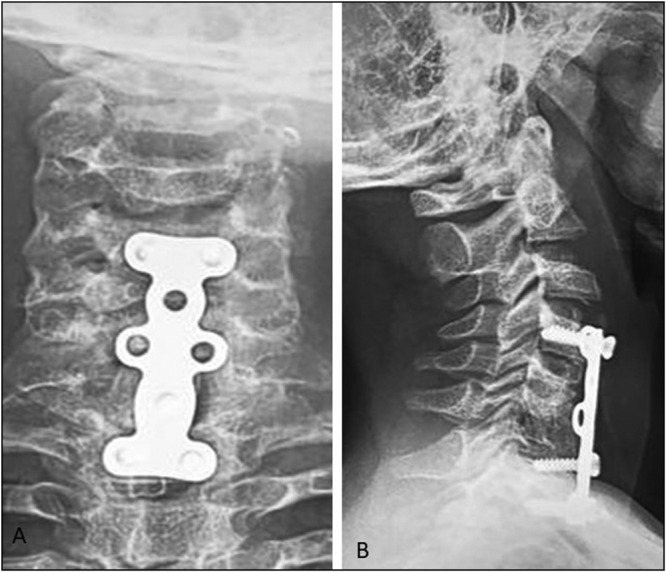

Case report: We describe a case of a 14-year-old male, who was admitted for cervicalgia with incomplete neurological deficit as a result of falling from a tree. Computed tomography (CT) of the neck revealed a posterior C5-C6 spondyloptosis with anterior spondylolisthesis of C7-T1. Surgical intervention was performed by the anterior approach only. The patient recovered completely after 2 months.

Conclusion: Traumatic cervical spondyloptosis is an injury with rare occurrence with varied clinical presentations. Until now, there is no consensus concerning the most effective treatment for spondyloptosis. Satisfactory clinical and good outcomes can be obtained by anterior cervical corpectomy and fusion.